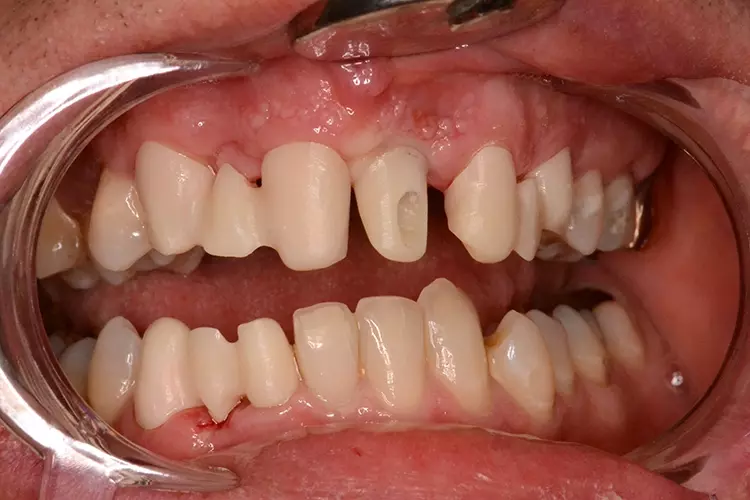

Neugestaltung der Front bei starken Zahnfehlstellungen

Bei dem heute 49-jährigen Patienten wurde seit Kindertagen versäumt, die Ober- und Unterkieferzahnbögen kieferorthopädisch auszurichten. Der Patient leidet seitdem stark unter seinen Zahnfehlstellungen.

Die Fraktur des stark elongierten Zahnes 21 war für den Patienten der Ausgangspunkt, sowohl die Front des Ober- als auch des Unterkiefers prothetisch überarbeiten zu lassen. Dabei wurde der frakturierte Zahn 21 durch ein navigiert eingesetztes Sofortimplantat ersetzt, während die verschachtelt stehenden Zähne 12 und 42 durch eine Brückenversorgung korrigiert wurden (Abb. 4a-j).